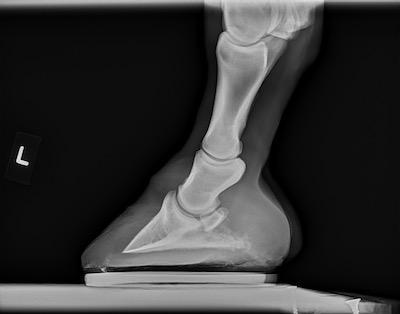

This painful condition is normally found on x-rays. The pedal bone, also known as the coffin bone, is inflamed, bruises, and has uneven edges.

Bone fractures in the hoof

The bones inside the hoof can fracture. Sometimes the outlook is good, and horses can recover from a broken bone in the foot.

X-rays are so important in the diagnostic process